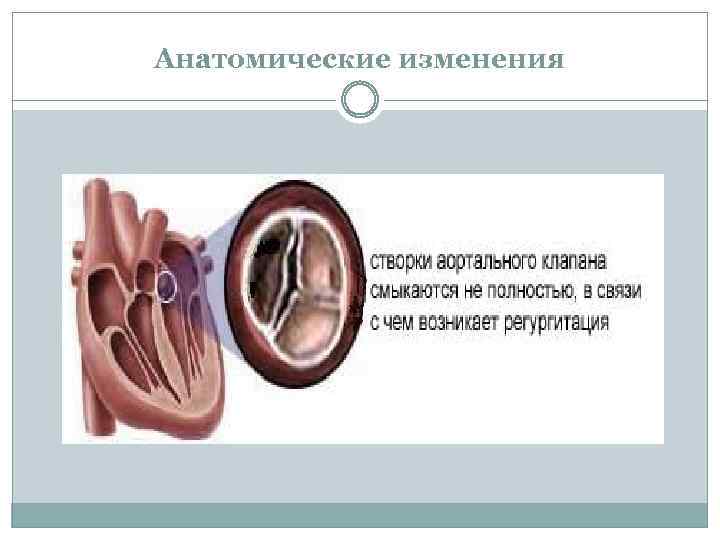

Анатомические изменения

Нарушения гемодинамики 1. Во время диастолы полулунные клапаны не смыкаются 2. Ток крови в силу градиента давления из аорты во время диастолы возвращается в левый желудочек 3. Возникает перегрузка левого желудочка объемом